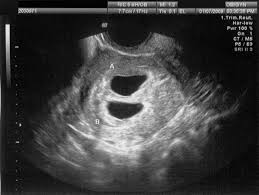

Ultrasound images in the first trimester of: By your 6th week of. Anonymous asked in pregnancy & parenting. Twins 4 weeks 6 days ultrasound this was taken at 4 weeks 6 days. Ultrasound uses sound waves to create an image of your babies in the womb. 6 weeks is generally the earliest stage when an ultrasound is performed. 1280 x 720 jpeg 53 кб. Twin pregnancy (fraternal twins) ultrasound pregnancy resulted from implantation of 2 genetically different embryos.

Belly pictures, symptoms & ultrasound. An early ultrasound can be helpful if you're not sure of. 6 weeks pregnant with twins belly pictures. Ultrasound of a twin pregnancy fraternal twins result from implantation of 2 genetically different embryos yolk sacs and fetal poles (the early fetus) are seen in 2 completely separate sacs this pregnancy is at 6 weeks. Reader noura i was kind enough to share ultrasound images of her di/di identical twins, whose ultrasounds look just like those of fraternal.